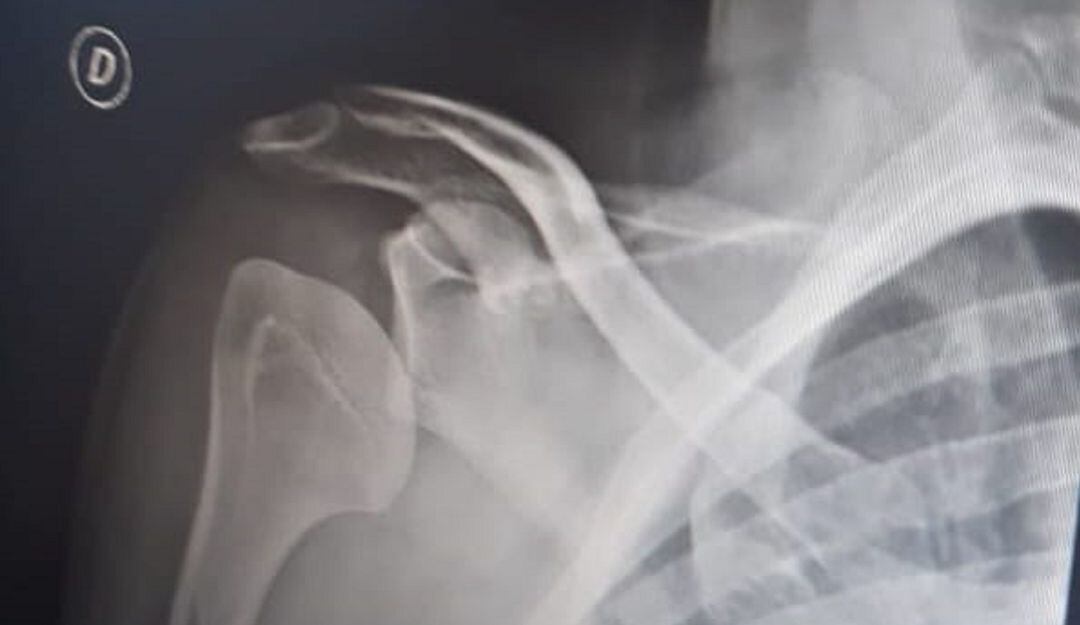

(Cortesía)

Al llegar a la clínica Versalles de la capital de Caldas, el especialista encendió las alertas: el hombro tenía los ligamentos totalmente rotos y le programaron, por lo menos, cuatro cirugías para su reconstrucción.